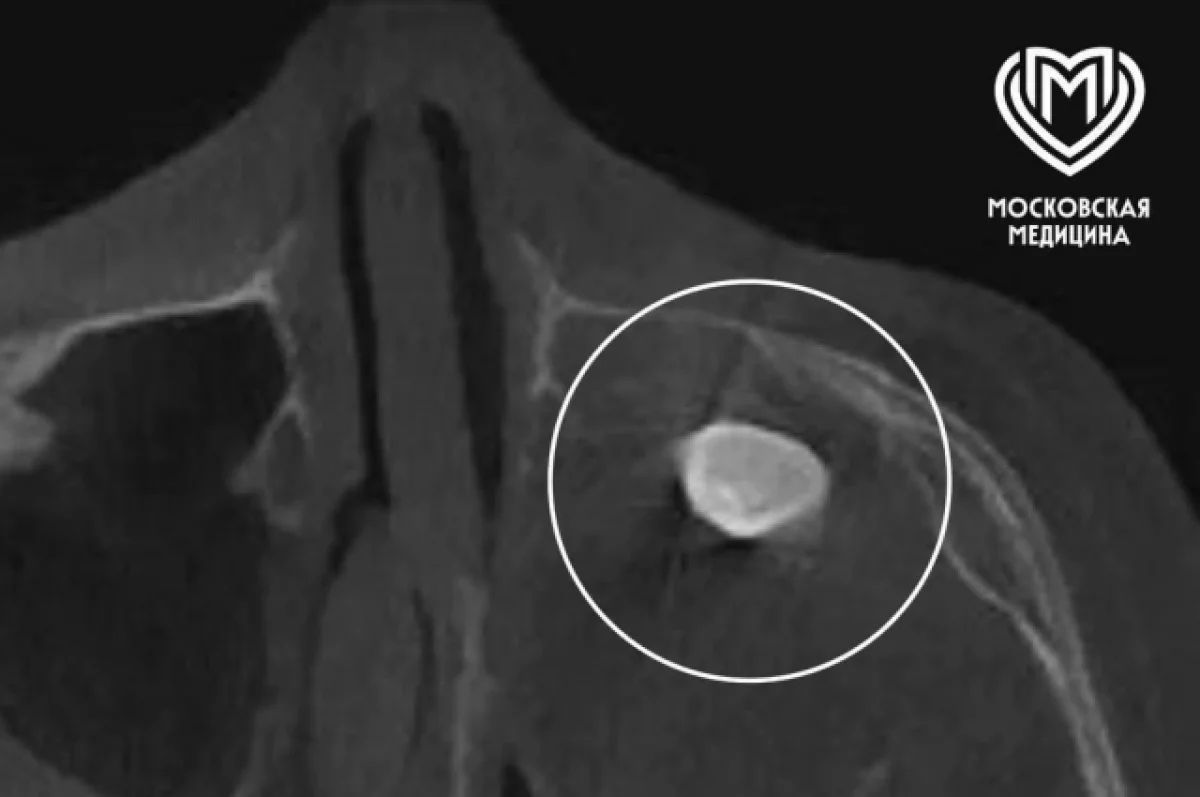

Ранее в частной клинике при обследовании в гайморовой пазухе у него выявили сформированный зуб. Родители, обеспокоенные предложенным методом удаления через полость носа, обратились за консультацией в Филатовскую детскую больницу.

Врачи провели углублённое обследование, собрали консилиум и решили оперировать через верхнюю десну по методу Колдуэлла—Люка. Во время вмешательства медики обнаружили новообразование, внутри которого находился зуб.

После исследования выяснилось, что это тератома — редкий тип эмбрионально‑клеточного новообразования, который может содержать элементы тканей, несвойственных для данной области тела. В данном случае тератома была доброкачественной и занимала практически всю левую полость носа — из‑за этого её не выявили на КТ и рентгене.